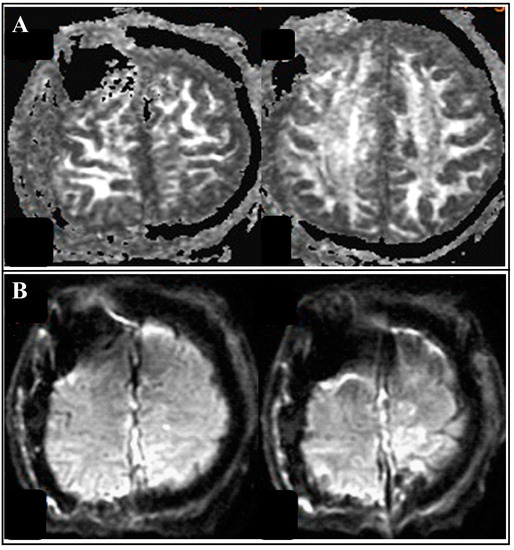

| Tsai et al., 2021 | 55/M | Seizure, loss of consciousness | 91 | bilateral | occluded | II | I | 2/5 left arm and left leg 0/5 right leg | Preserved | Aphasia | Aphasia recovery within 7 days; muscle power recovery within 7 weeks |